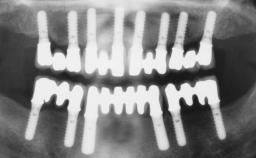

Conventional Loading of Eight Implants in the Maxilla and Final Restoration with a Full-Arch Gold-Ceramic FDP

A 35-year-old Caucasian female presenting with advanced periodontal disease involving both the maxillary and the mandibular dentition was referred for evaluation. The patient, a non-smoker in good general health, requested treatment for recurrent periodontal abscesses, tooth mobility, and discomfort during chewing, as well as restoration of her missing teeth with a fixed prosthesis to improve mastication and esthetics. All residual maxillary teeth exhibited plaque deposits, deep pockets, bleeding on probing, and class III mobility and were evaluated as hopeless. All residual mandibular teeth except tooth 37 could be maintained after periodontal therapy.

# of Implants 8

Type of Implants One-Piece

Prosthesis Type FDP

Defining Characteristics Fully edentulous upper jaw to be rehabilitated with four or more implants

Modality Fixed hybrid bridge on 5+ implants

Defining Characteristics Fully edentulous upper jaw to be rehabilitated with an implant-borne fixed dental prosthesis